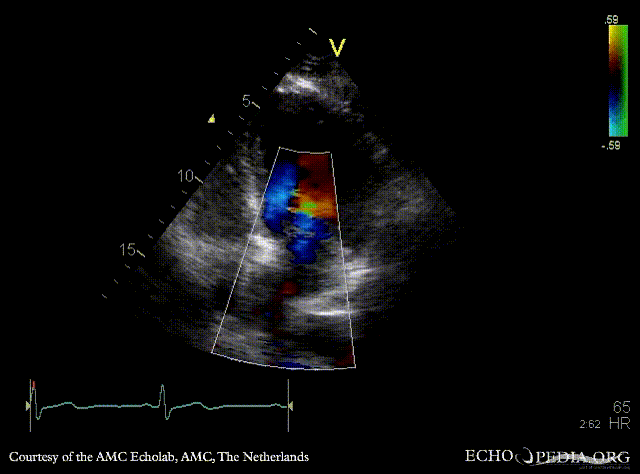

Cor triatriatum

A4CH: Color Doppler